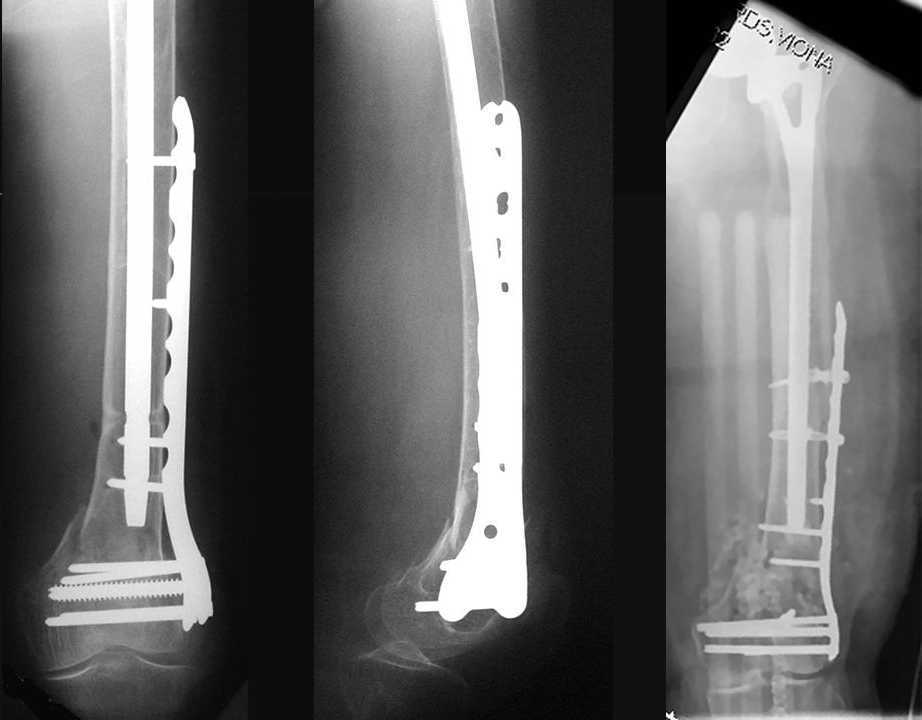

4. We could treat this fracture like there is no a nail - new locking plates allow for secure fixation.... two similar cases are attached...